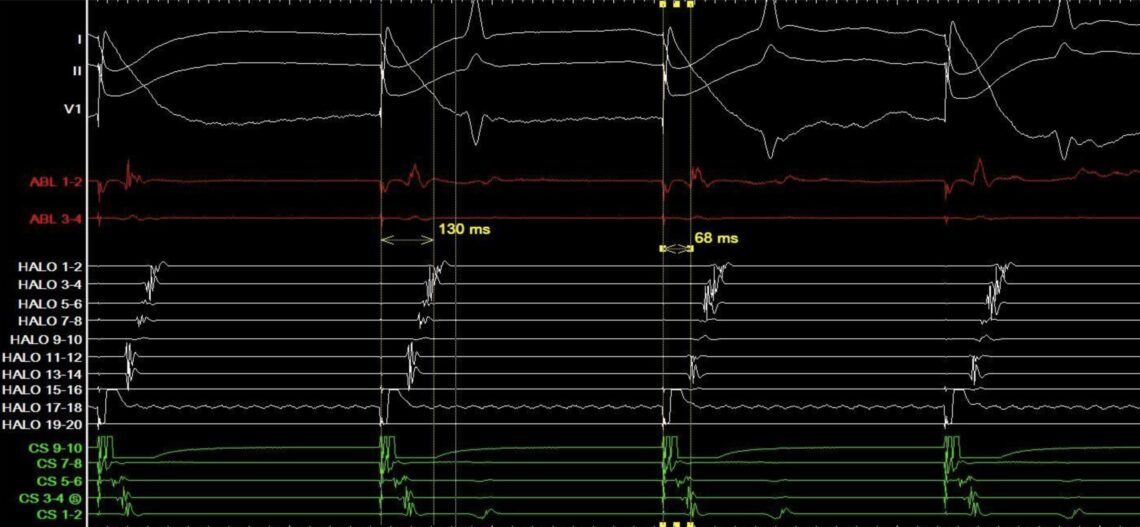

A 57-year-old man with a history of palpitations and no structural heart … Continued